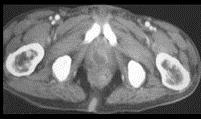

问题 男,35岁,右侧腰部疼痛伴发热,请根据所示图像,选择最可能诊断 ( )

选项 A、右肾转移瘤 B、前列腺脓肿 C、右侧单纯性肾囊肿 D、右侧囊性肾癌 E、右侧肾脓肿

答案 BE